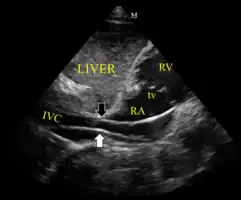

Ultrasound showing the device in the right ventricle

The device inappropriately passing into the inferior vena cava